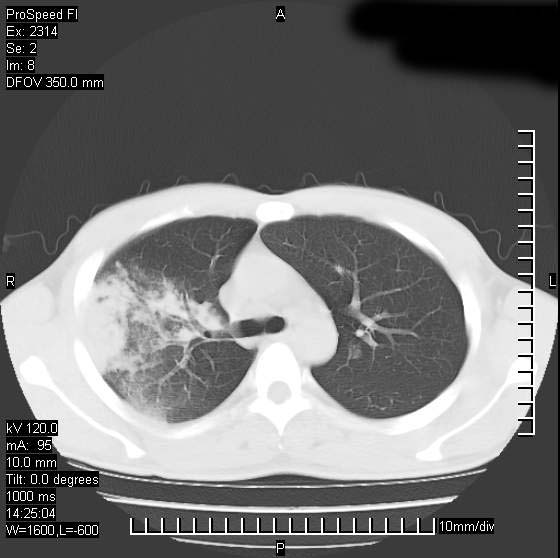

男性,再生障碍性贫血,入院前发热10天,最高40c,右侧胸痛,外院ct示右上,中肺边缘模糊的球性影(就是我现在图中标示的范围),考虑炎症,在我院使用头孢呋辛,洛美沙星10天,高烧消退,自感下午稍有发热,但今天ct示右上,中肺病灶明显扩大,还是考虑炎症,看其中的球型影是否霉菌感染??,是否能排除结核?

右肺中叶外侧段病变,上缘界限不清,下缘锐利,以段性发病为主,内见巨大空洞及空洞内容物,结合病史首先考虑:化脓性肺炎。不除外霉菌感染!

考虑霉菌感染.理由1\\有临床基础疾病,2\\有坏死的空腔,其内可见软组织影.

片状高密度影内见空洞影,内可见球形软组织密度影,并有新月征,考虑霉菌感染.